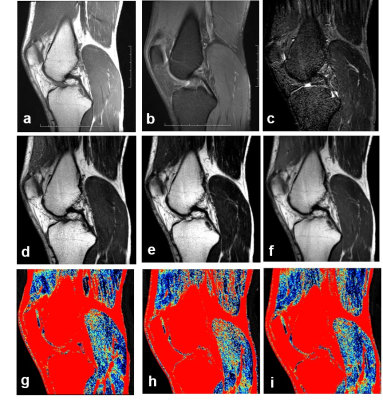

Conventional and synthetic MRI images of the medial head of gastrocnemius muscle in amateur marathon. Conventional T1WI sequence (a) and PD weighted fat suppression sequence (b), synthetic MRI T2WI -TIRM sequence (c), synthetic MRI T1WI (d), synthetic MRI T2WI (e) and synthetic MRI PD weighted image (f) can clearly show the morphology of the medial head of gastrocnemius muscle. A pseudo color diagram of T2 value of dynamic change of medial head of gastrocnemius muscle(g-i).The results showed that T2 value increased 48 hours after running and decreased 1 month after running.